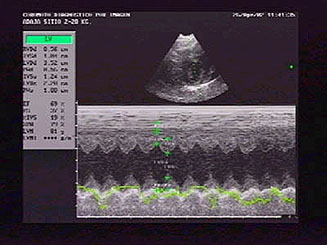

En el modo B y en el corte para-esternal derecho de

4 cámaras en eje largo, se observó una

cardiomegalia generalizada con prominencia del ventrículo

y atrio derechos (la sobrecarga de volumen ventricular

causa una dilatación diastólica ventricular

sin afectación del grosor de la pared, "dilatación

excéntrica" y función sistólica

normal). |

El movimiento paradójico del septo interventricular

secundario a la sobrecarga de volumen del ventrículo

derecho se observó claramente en el modo M, concretamente

en el corte transversal para-esternal derecho del ventrículo

izquierdo. Muchos de los corazones estudiados presentaban

derrame pericárdico, todos zonas hiper-ecogénicas

(compatibles con fibrosis) en el miocardio del septo

interventricular y alguno contraste ecográfico

espontáneo signo presuntivo de trombo-embolismo.